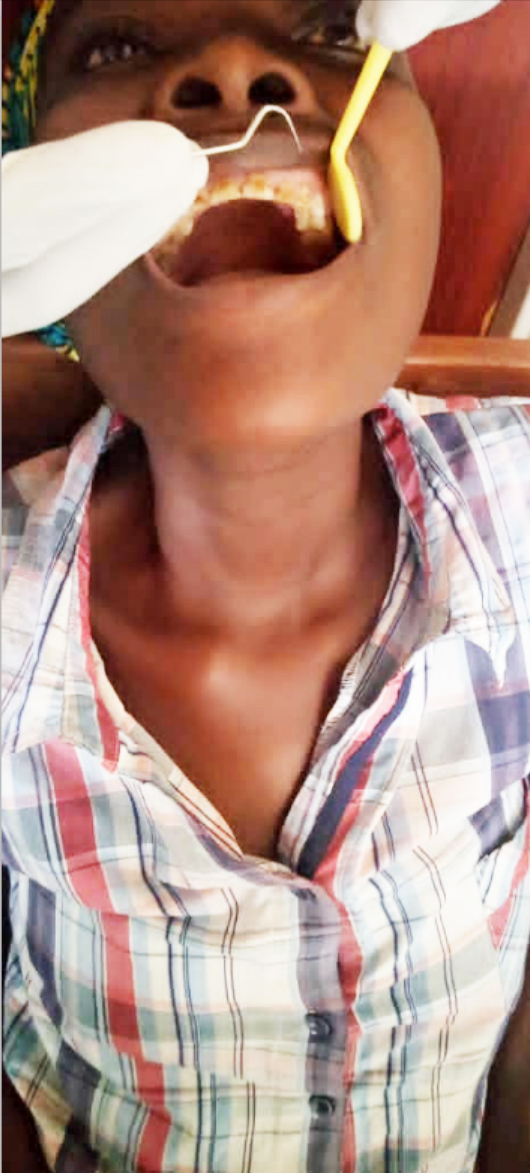

Oral Health Solutions Organization (OHSO), founded in October 2019, is an active non-governmental organisation (NGO) at the forefront of improving oral health in Rwanda, through oral health promotion, oral disease prevention and advocacy. The NGO vies to complement adequately Government effort to promote health and prevent diseases through school and maternal health settings. We adopt proactive engagement across all platforms in working alongside various government ministries, institutions,NGOs,dental professionals and the public.